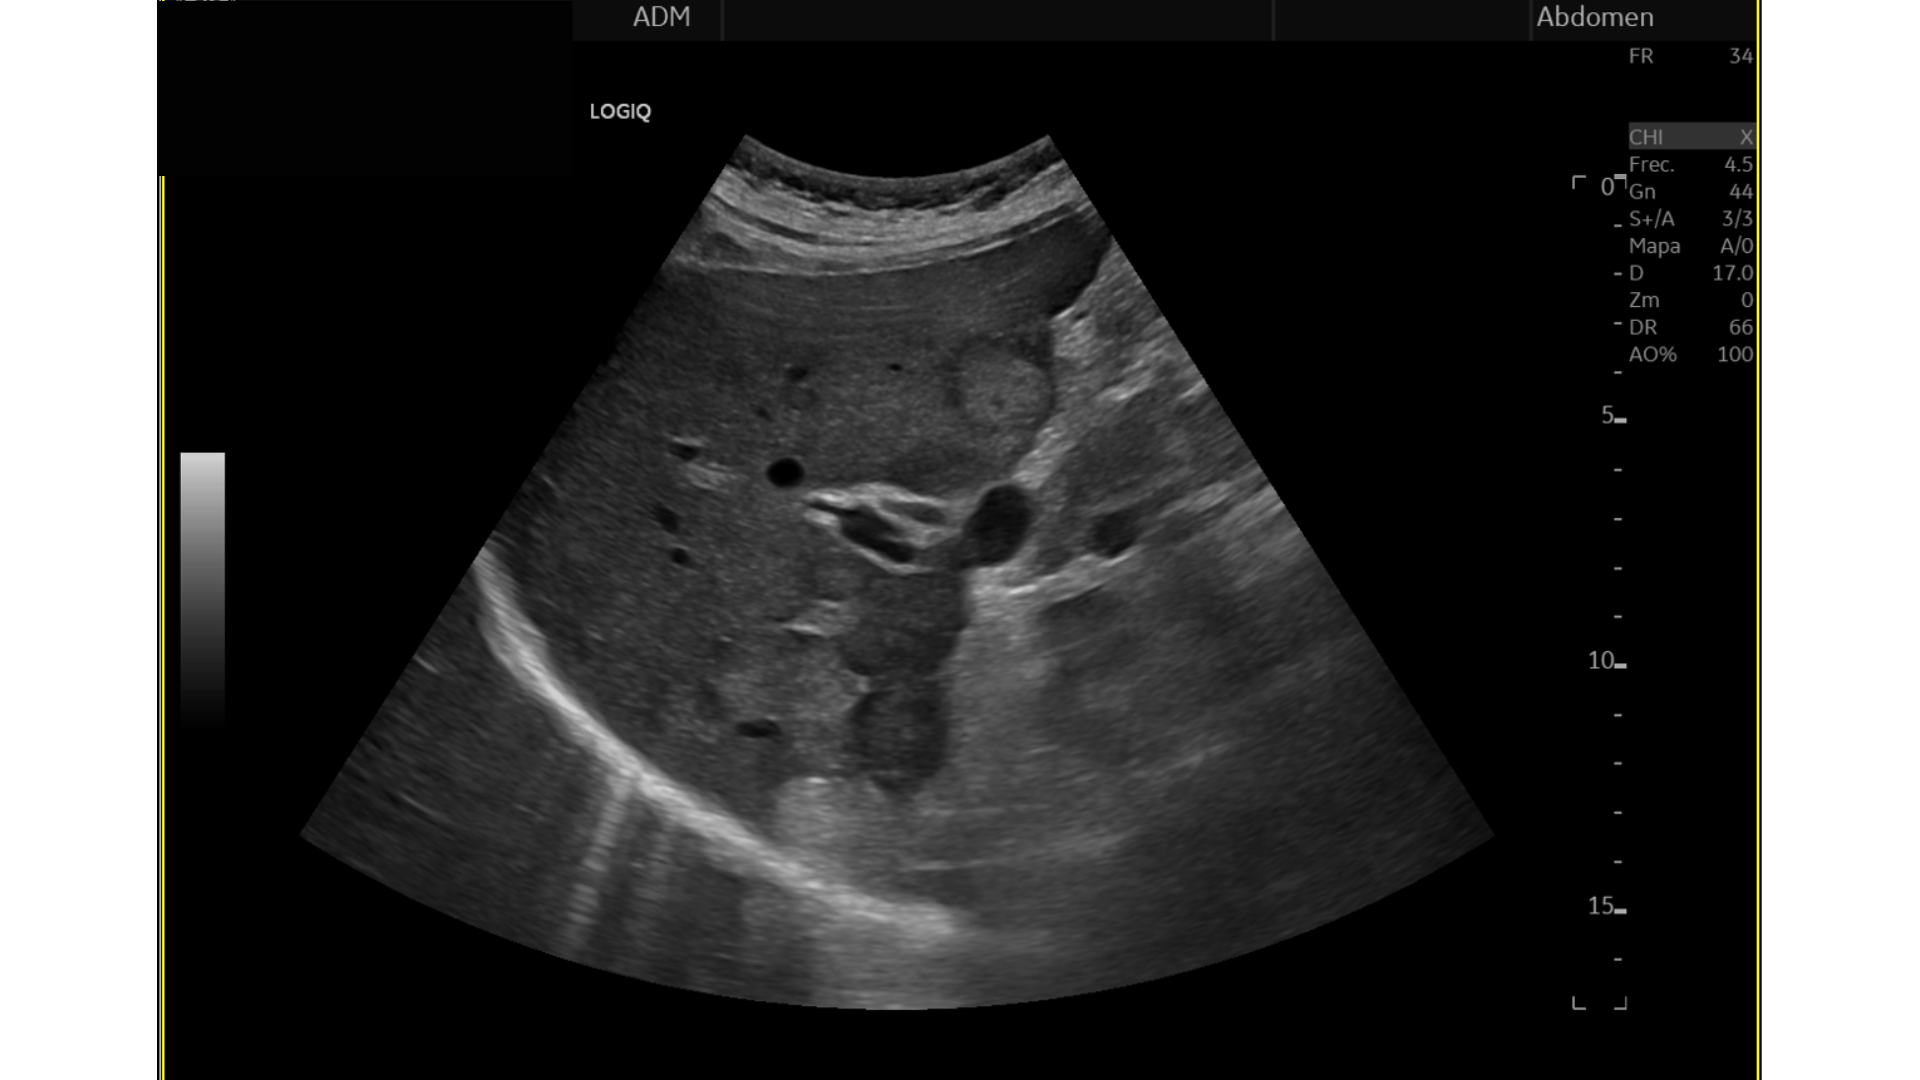

Eco Abdominal: Múltiples imágenes nodulares heterogéneas en ambos lóbulos hepáticos sugestivas de M1. Destaca imágen nodular, hipoecogénica en cabeza/cuerpo de páncreas de aprox. 17 mm, podría corresponderse con proceso neoformativo primario.